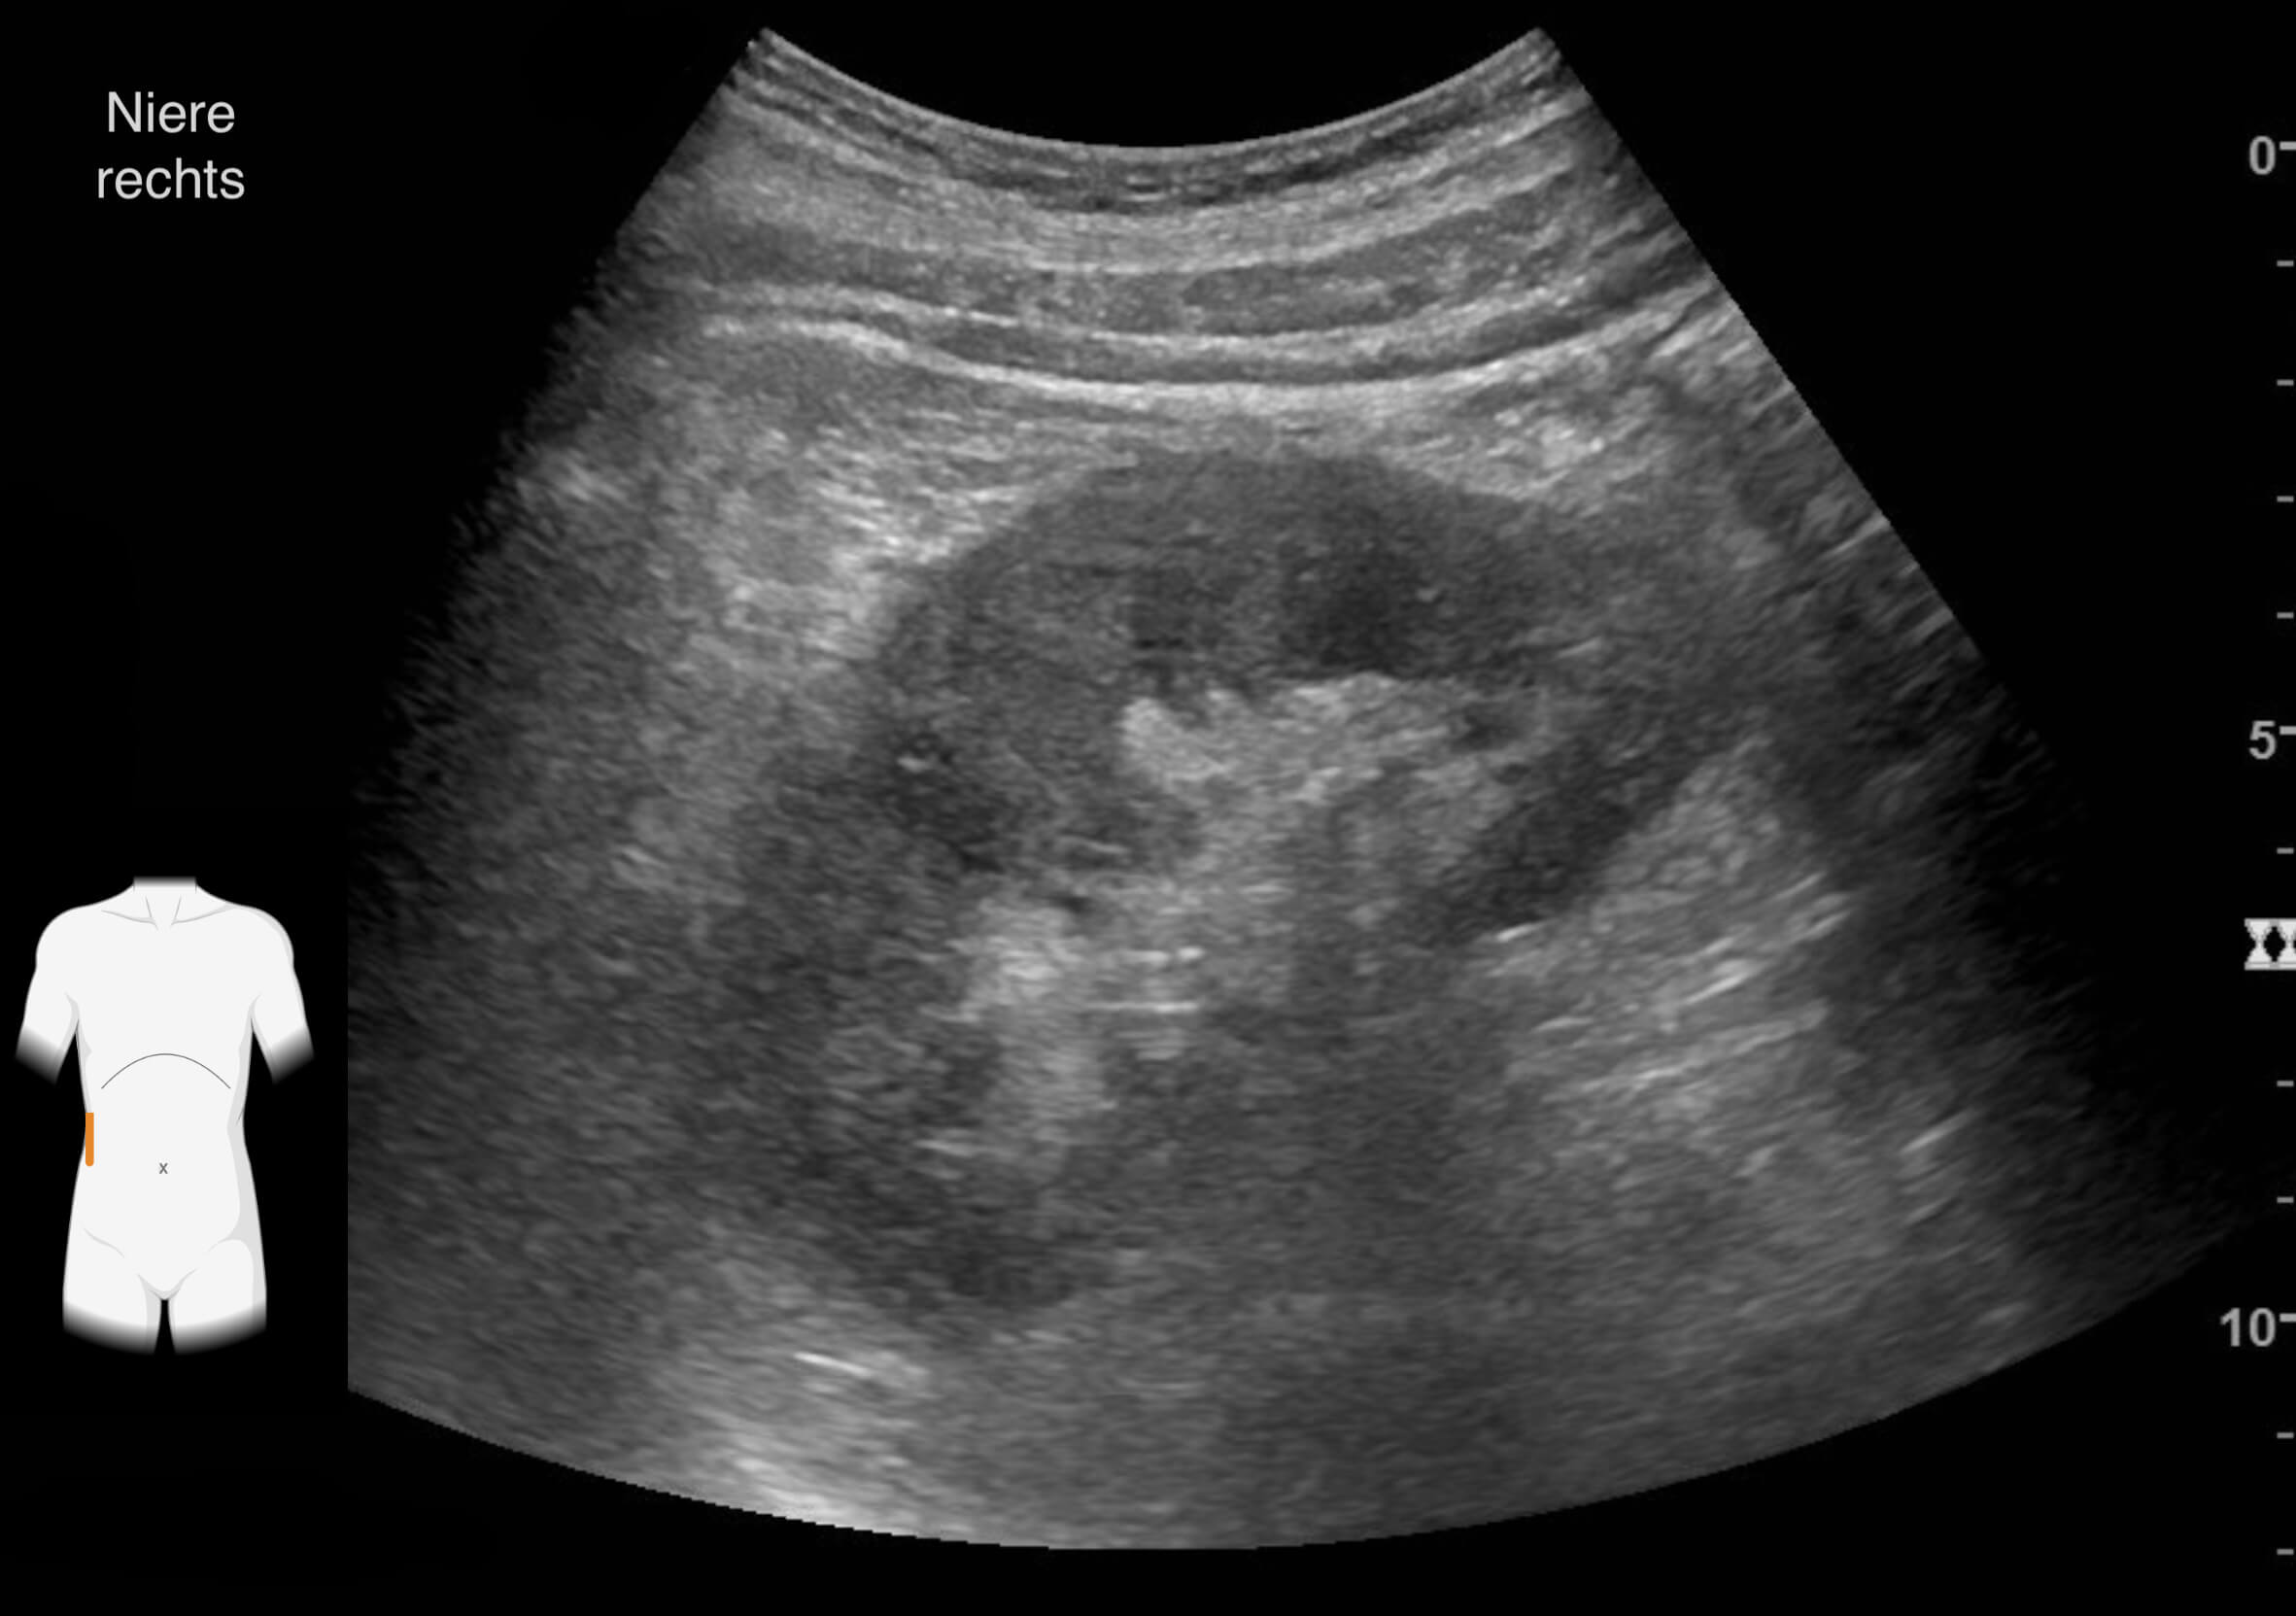

Die Ergebnisse der durchgeführten Untersuchungen kannst du dir hier anschauen:

Die Befunde geben eindeutige Hinweise auf die Erkrankung von Frau Lorenz. Wie bewertest du die Ergebnisse?